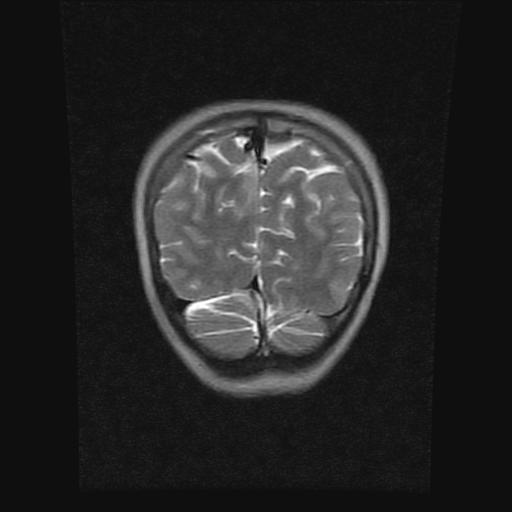

9岁女孩,三岁时诊断为癫痫,一直服丙戊酸钠,现患者一般情况良好,家长复查核磁片,看能否停药..

巨脑回

未见异常信号灶.

未发现异常信号。